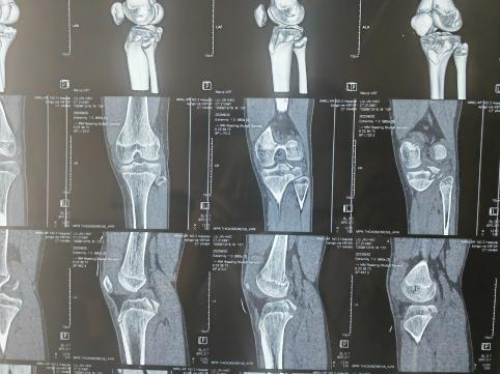

术前核磁光片